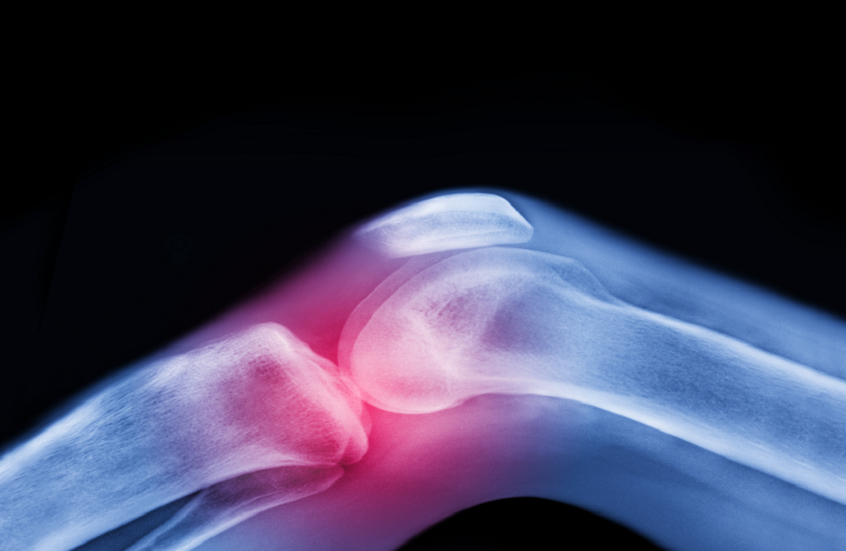

دواء شائع للسكري يخفف آلام التهاب مفاصل الركبة

وأظهرت الدراسة أن الميتفورمين، المستخدم عادة لعلاج السكري من النوع الثاني، يمكن أن يساعد في تخفيف آلام الركبة الناتجة عن هشاشة العظام لدى الأشخاص الذين يعانون من زيادة الوزن أو السمنة، ما قد يؤخر الحاجة إلى عمليات استبدال الركبة.